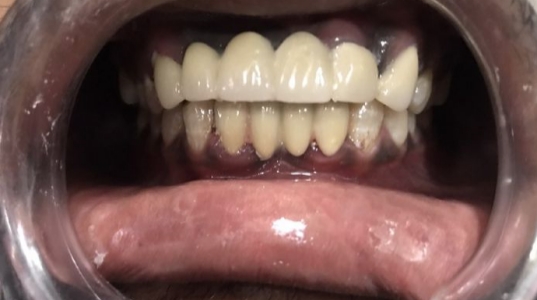

At Pranjal Dental Clinic, we offer a wide range of advanced dental treatments in Greater Noida to ensure complete oral health and beautiful smiles. Our services include root canal treatment, dental implants, smile designing, teeth whitening, cosmetic dentistry, tooth extraction, and painless dental care. With modern technology and expert care by Dr. Pranjal Sirohi, we provide safe, effective, and comfortable dental solutions for patients of all ages.